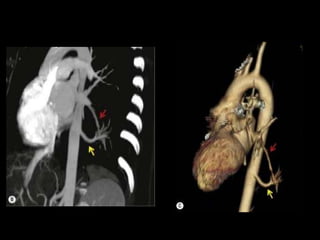

Malformação arteriovenosa(MAV) MAV congênitas: fístulas vasculares com comunicação entre a artéria e a veia pulmonar(95%) ou de uma artéria sistêmica e a veia pulmonar com by-pass do leito capilar; Cerca de 50% das MAVs estão associadas com Síndrome de Rendu-Osler-Weber(teleangiectasia hemorrágica hereditária); O diagnóstico costuma ser bem direto pela TC;

Malformação arteriovenosa(MAV) TC:o aspecto típico é de uma massa regular, lobulada, redonda ou oval, ou até o de uma formação serpenginosa, com menos de 1 cm a vários cm de tamanho, associada a uma artéria nutriz visivelmente aumentada e uma veia de drenagem alargada; Uma ANGIO-TC geralmente faz o diagnóstico; Tratamento pode ser realizado com terapia embólica.